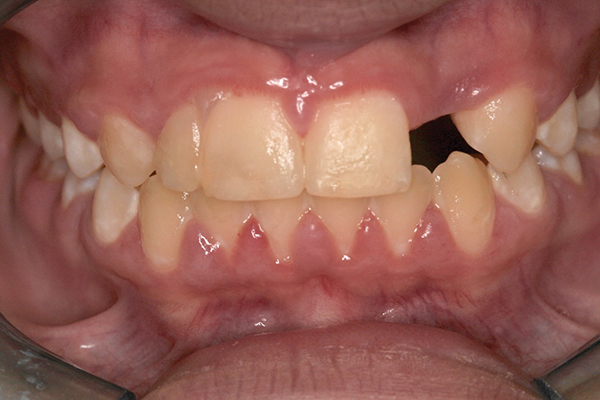

Fig 1 and Fig 2. Pretreatment photographs. Patient at 9 years of age on presentation.

A 9-year-old girl, referred to a prosthodontic office by her pediatric dentist, presented with her mother’s chief complaint: “The kids are teasing her about her big front tooth.” Findings from radiographic and clinical examinations revealed fused maxillary central-peg lateral incisors, teeth Nos. 7 and 8, and a congenitally missing lateral incisor, tooth No. 10 (Figure 1 through Figure 3). An implant was selected as the ideal treatment to replace tooth No. 10 when somatic growth was complete. A diagnostic wax-up was fabricated to determine if the fused tooth could be made to resemble two teeth, using pink composite to give the illusion of an interproximal papilla. The patient was referred for an orthodontic consultation to plan for closure of the diastema between teeth Nos. 8 and 9 and achievement of proper alignment for implant No. 10. The patient was also referred to a periodontist for pretreatment assessment of the tooth No. 10 site. An endodontist was consulted should exposure of the large pulp occur during tooth preparation.

Using the wax-up as a guide, a composite restoration was fabricated for fused teeth Nos. 7 and 8 by roughening the affected area without pulpal exposure, etching the enamel, and applying primer and adhesive. Composite shade A1 was bonded to the mesial and distal surfaces, with gingival dark composite applied to the cervical “interproximal” region. The tooth was then carved to resemble two teeth, matching the width of the created tooth central to tooth No. 9 (Figure 4 and Figure 5). The patient and her family were very pleased with the result, and no postoperative sensitivity was reported.